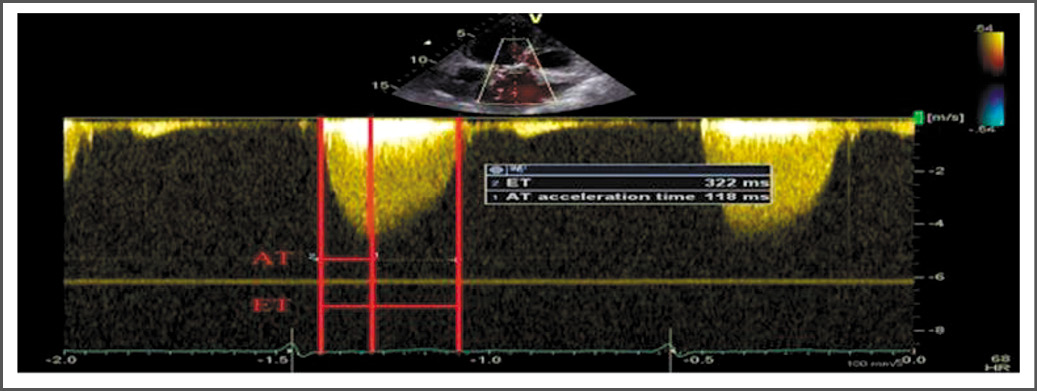

Мультиспиральная компьютерная томография

Для дифференциальной диагностики дву- или трёхстворчатого строения АК пациентам проводили мультиспиральную компьютерную томографию (МСКТ). МСКТ выполняли в том случае, если в результате ЭхоКГ не удавалось достоверно определить анатомию клапана. Исследование было выполнено у 114 (61%) пациентов. МСКТ-ангиографию выполняли на компьютерном томографе «Somatom Sensation» (Siemens, Германия), (рис. 2).

Рис. 2. Оценка строения аортального клапана с помощью мультиспиральной компьютерной томографии. А – аортальный клапан с трёхстворчатым строением, Б – аортальный клапан с двустворчатым строением. / Fig. 2. Assessment of the structure of the aortic valve using multispiral computed tomography. A – aortic valve with a tricuspid structure,B – aortic valve with a bicuspid structure.